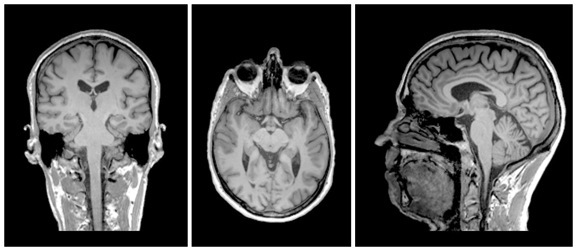

plan coronal

ou frontal

plan horizontal

plan sagittal

plan coronal

ou frontal

plan horizontal

plan sagittal